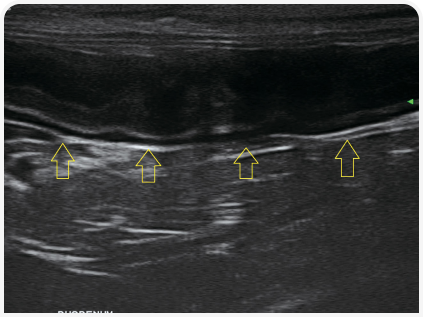

Полезным дополнительным инструментом при поиске причин рвоты может стать ультразвуковое исследование органов брюшной полости. При признаках расслоения стенки кишечника исключают линейные инородные тела (Рисунок 4), хотя иногда такие изменения неверно истолковывают как складчатость (Рисунок 5) — неспецифичный симптом, описанный у кошек при энтерите, панкреатите, перитоните, новообразованиях (5). Также можно оценить изменения архитектоники, например утрату структуры слоев или утолщение стенки ЖКТ.